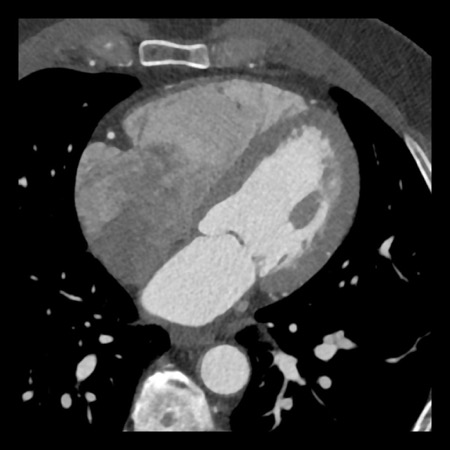

case 4 – CAD-RADS 3/P1/I+ thrombus left ventricle

First, scroll through the CTA images.

How would you describe the findings on the coronary CTA?

The findings are:

- Moderate (50-69%)

stenosis in the proximal LAD caused by a non-calcified plaque. - Variant of

sinoatrial (SA) nodal artery. The artery usually arises from the RCA as a second

branch after the conus artery, however in this case it arises from the LCX,

courses behind the aorta, anastomosing with the right atrium and with a small

branch supplies the SA-node of the heart. - Thrombus in the

apex of the left ventricle. - CTP was performed

in this patient. CTP showed a perfusion defect at stress imaging in the

territory of the LAD (I+), at rest no perfusion defect was visible.

This patient classifies as CAD-RADS 3/P1/I+, which means

this patient requires further investigation.